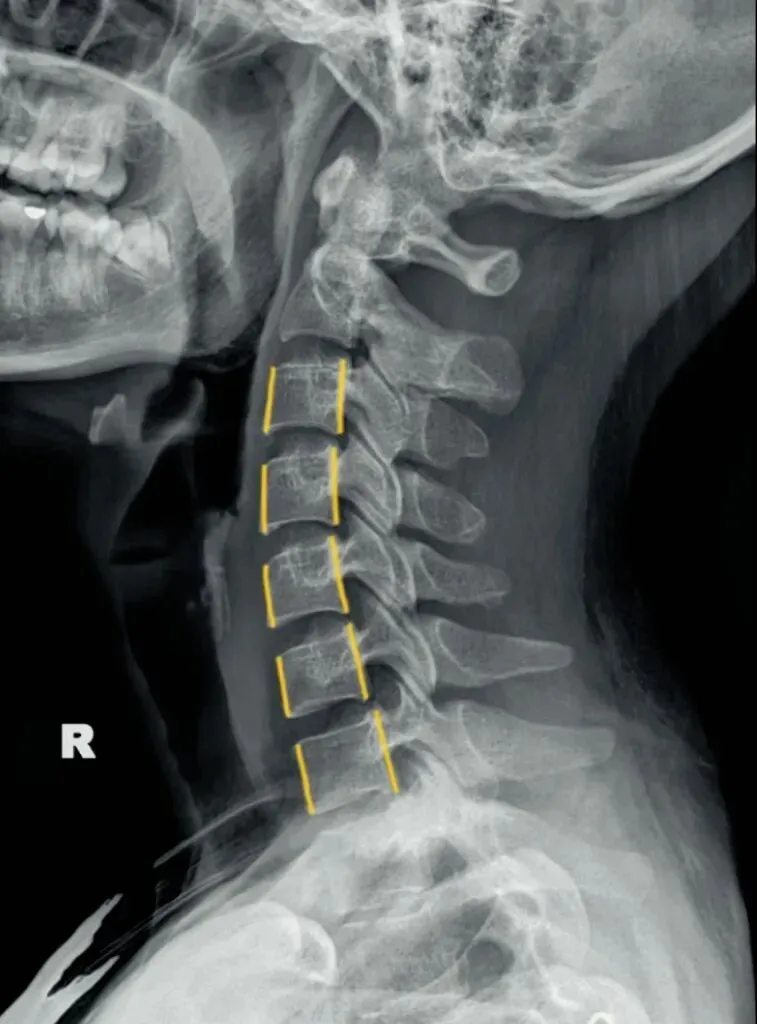

二弓指的是颈椎生理曲度,在颈椎侧位X线片中,正常生理状态下呈现向前凸出的弧形曲线,呈半C型前凸类似弓形,是人体脊柱生理曲度的重要组成部分。颈椎曲度变化能够反映颈椎整体功能的变化。

常见的颈椎曲度改变有曲度变直和曲度反曲。

颈椎生理曲度测量的方法多种多样,其中应用最广泛的测量方法是Borden法。从齿状突后上缘开始向下将每个椎体后缘相连成为一条弧线,然后从齿状突后上缘至C7椎体后下缘作一直线测量,两条线间最宽处的垂直横交线的距离即为颈椎生理曲度深度。

正常时,最宽处在C4椎体水平正常为12毫米,正负5毫米,小于7毫米为生理曲度变直,大于17毫米为生理曲度过度前屈,小于零时为生理曲度反曲。